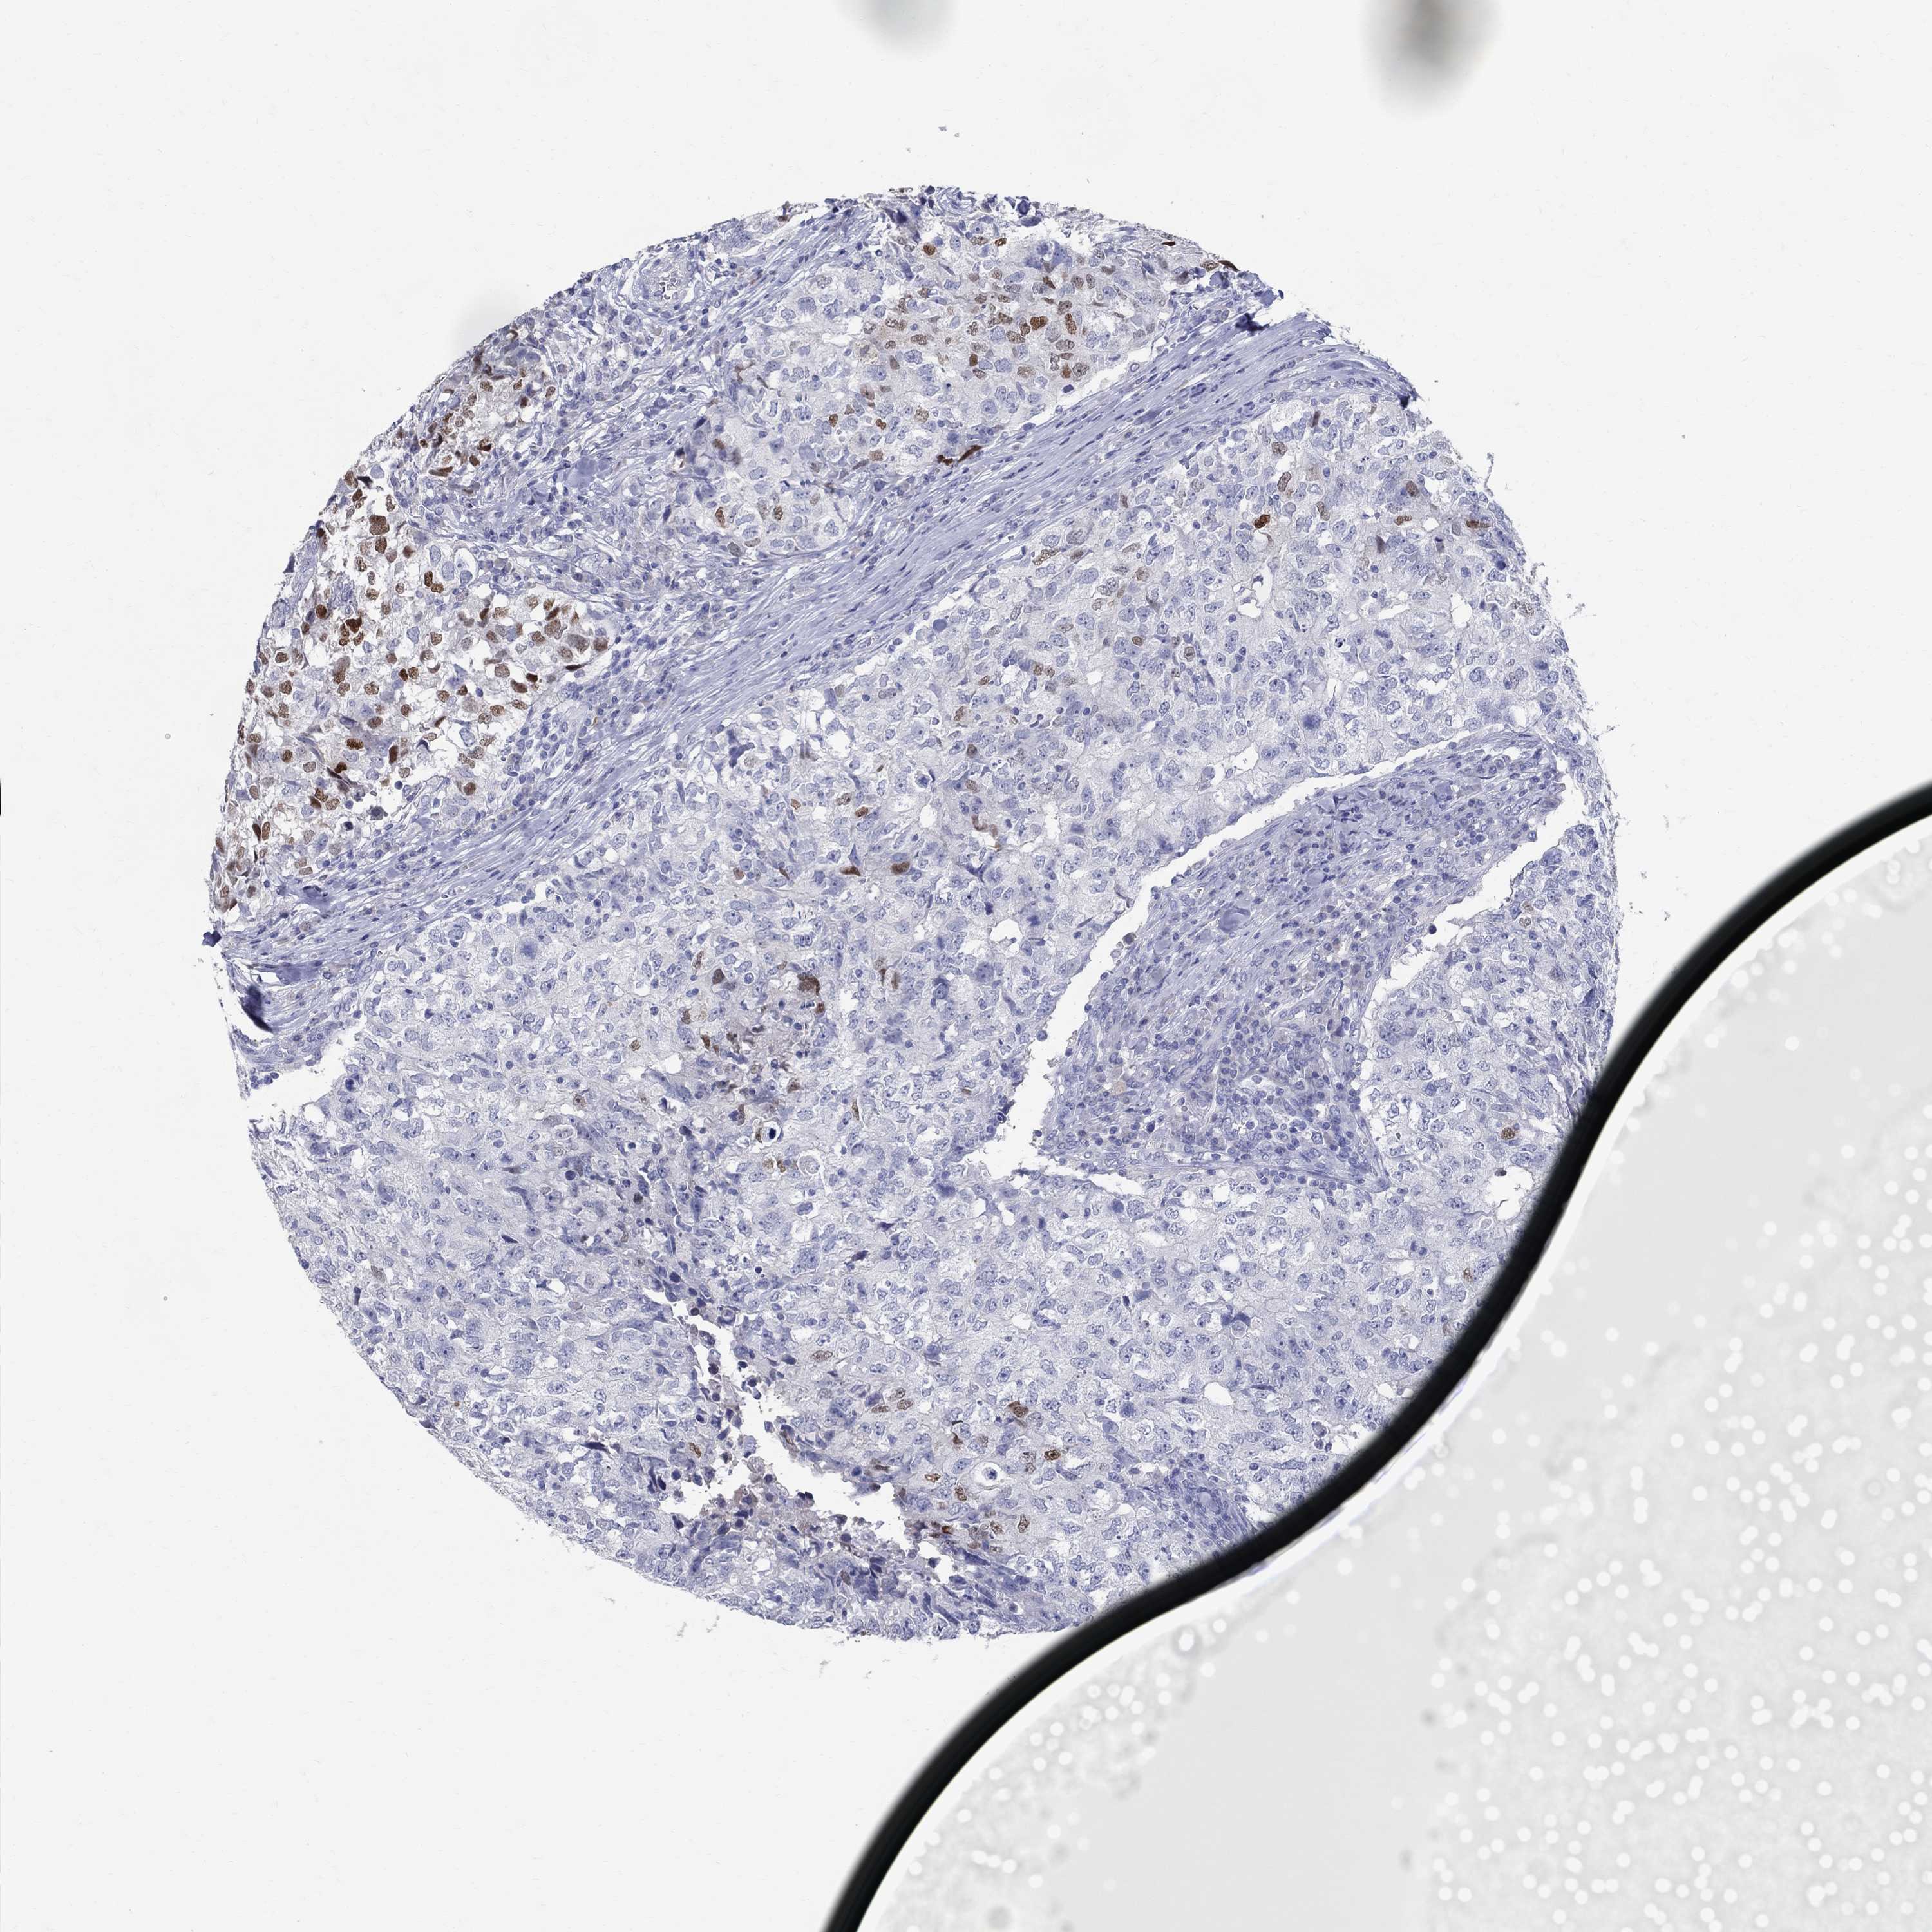

BRCA TCGA BRCA VALIDATION PROTEIN EXPRESSION

ANTIBODIES

AND

VALIDATION